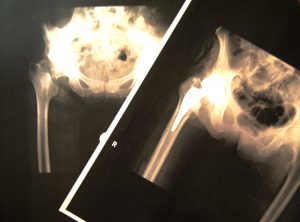

大腿骨骨折後のリハビリ(自宅編)

大腿骨骨折後には、筋力低下、バランス低下を呈することがあり、国内ではほとんどの場合は手術の適応となります。

大腿骨頸部骨折後のリハビリ